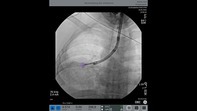

Lung abscesses represent complex localised infections of the lung parenchyma. If they fail to resolve with conventional medical and surgical therapy, they pose a significant clinical challenge, particularly when the lesion is poorly accessible to percutaneous or open drainage. The evolution of advanced bronchoscopic techniques including cone-beam computed tomography (CBCT) and superimposed high-frequency jet ventilation (SHFJV) now allows for precise, minimally invasive interventions in such complex cases. We report a case of a persistent right upper lobe abscess due to invasive pulmonary infection that was successfully drained bronchoscopically. CBCT imaging enabled real-time, three-dimensional localisation and confirmation of needle placement within the abscess cavity. SHFJV, delivered through a jet converter system and endotracheal tube, stabilised the lung and minimised motion artefact during imaging and intervention. This case highlights the potential for bronchoscopic intervention in the multidisciplinary management of complex pulmonary infections. This procedure, performed entirely through flexible bronchoscopy, demonstrates how newer technical innovations enhance procedural accuracy, improve safety, and expand the therapeutic potential of interventional pulmonology beyond the traditional confines of rigid bronchoscopy.